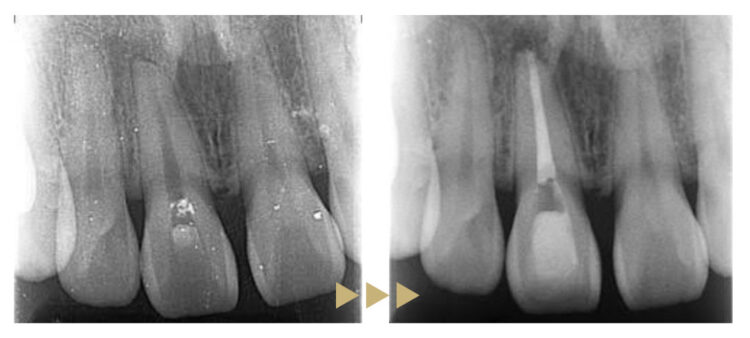

治療前の状態

右上前歯は歯の神経が死んでしまったことによる変色がありました。また左上前歯との間に隙間がありました。

治療後の状態

右上前歯を根管治療後、セラミッククラウンにて補綴、左上前歯をダイレクトボンディングで修復し、スペースを閉鎖しました。